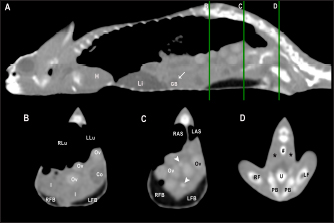

Fig. 7. Sagittal right paramedian postcontrast CT image displayed in soft tissue window (A) and selected corresponding transverse images represented as green line section, displayed in soft tissue window, at the level of intestines (B), fat bodies and ovaries (C), and urinary bladder (D) in a female veiled chameleon (C. calyptratus). H, heart; GB, gallbladder; arrow, enhancement of the gallbladder; RLu, right lung; LLu, left lung; Ov, ovaric follicles; Co, colon; I, intestine; RFB, right fat body; LFB, left fat body; RAS, right air sac; LAS, left air sac; arrowhead, ovarian vessels; #, caudal vein; *, Li, liver; kidneys; U, urinary bladder; RF, right femur; LF, left femur; PB, pelvic bone.

The gallbladder could be identified in the caudoventral border of the liver, between the two lobes, located in the ventral aspect of the medium coelom. It was slightly lateralized to the right side of the body and the intestinal loops and fat bodies were its caudal landmark. The gallbladder was observed in all veiled and panther chameleons as a fluid attenuating circular structure (Figs. 5 and 6) with no visible wall in precontrast images. In postcontrast images, the thin wall of the gallbladder enhanced homogeneously, and the content was hypoattenuating in comparison with the liver parenchyma (Fig. 7).

Gallbladder measurements are provided in Table 1 and attenuation values in Table 2.

Fig. 8. Sagittal precontrast CT image displayed in soft tissue window (A) and selected corresponding transverse images represented as green line section, displayed in soft tissue window at the level of the liver (B), ovaries (C), and kidneys/fat bodies (D) in a female panther chameleon (F. pardalis). E, eggs; RLi, right liver lobe; LLi, left liver lobe; ROv, right ovary; LOv, left ovary; RK, right kidney; LK, left kidney; LFB, left fat body.

The ovaries were identified cranial to the kidneys in 4 of 10 (40%) female veiled chameleons. They could be visualized as a cluster of multiple circular structures, the ovarian follicles, (with a grape-like appearance) with soft tissue attenuation in 2 of 10 (20%). Mild diffuse enhancement of these structures could be observed after contrast administration (Figs. 7 and 8). The diameter of the follicles ranged from 0.19 to 0.40 cm. When eggs were seen (2/10, 20%), they appeared as ovoid structures with alternating hyper and hypoattenuating layers (Fig. 8). The center of the egg had fluid attenuation and the peripheral line with mineral attenuation was the shell. The size of the eggs ranged from 0.56 to 0.80 cm in width and from 0.93 to 1.70 cm in length in veiled chameleons. The precontrast attenuation range of ovarian follicles was 25.5–39 HU in female veiled chameleons depending on the stage of follicle and egg development. The postcontrast attenuation range was 31.10–44.25 HU.